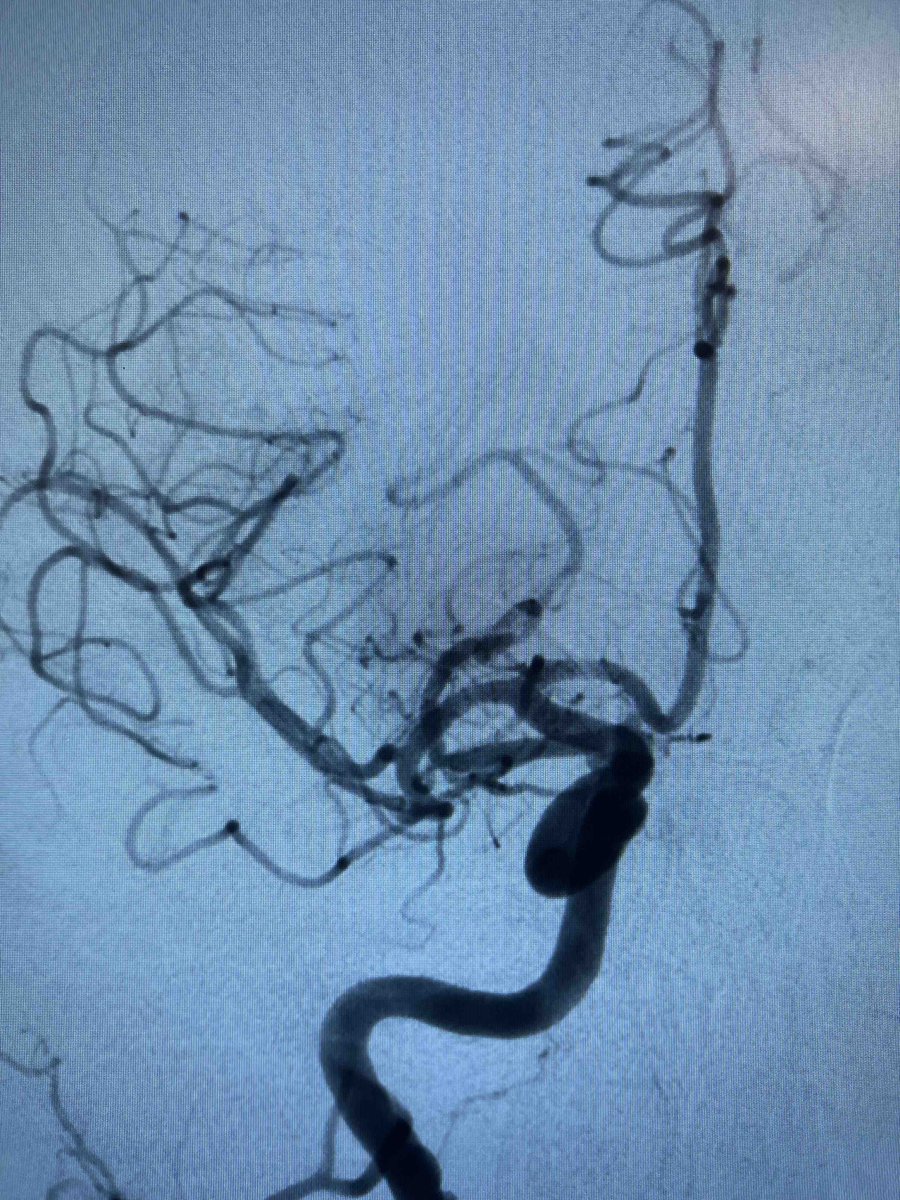

US HCPs: Check out this fantastic first pass result using RED 43 in left M2 from Dr. Amir Khan out of OC, CA! No clinical deficits or MRI infarct observed post thrombectomy. Thank you for sharing! #RED43 Rx only. Risk info: bit.ly/2BYj7Yj. Clinical results may vary.